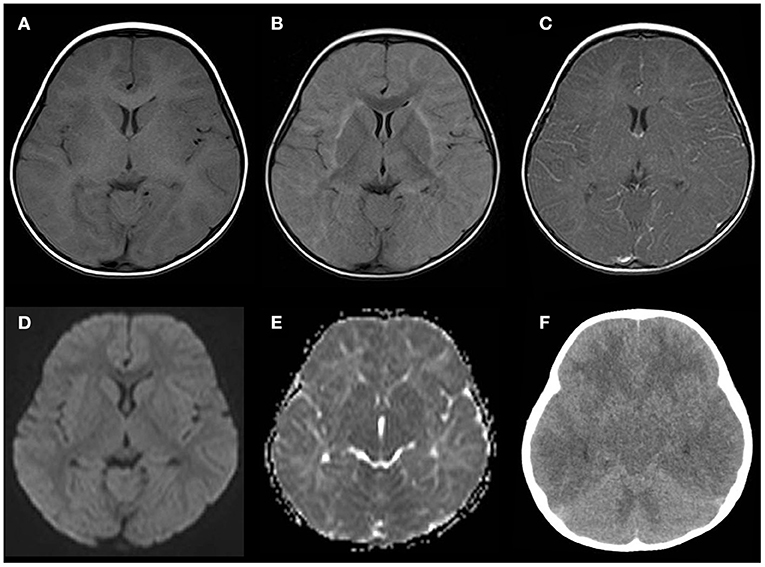

Several convulsive seizures were observed on day 13. Moreover, the patient's mental status started to worsen and she became lethargic. MRI T2-weighted images (T2WI) showed bilateral symmetrical hyperintensities in the cerebral white matter and thalamus. The white matter lesions were observed predominantly in the subcortical white matter and sparsely in the internal capsule and corpus callosum (Figure 1). Linear radial hyperintensities parallel to the cerebral vessels of the periventricular space were also observed (Figure 1C). The white matter lesions were isointense on a T1-weighted image (T1WI), and there were hyperintense signals on fluid-attenuated inversion recovery (Figures 2A,B). The lesions showed no gadolinium enhancement (Figure 2C). The cerebral white matter displayed iso-intensity on diffusion-weighted images (Figure 2D), with high intensity on the apparent diffusion coefficient map (Figure 2E). These findings suggested vasogenic edema. Susceptibility-weighted images did not show any hemorrhages.

Figure 2. Neuroimaging findings on days 13–14. (A–E) Several sequences of the head MRI on day 13. (A) Isointense white matter lesions on a T1-weighted image (T1WI). (B) Fluid-attenuated inversion recovery image showing a high intensity in the subcortical white matter and external capsule. (C) Post-gadolinium T1WI showing no enhancement in the white matter or perivascular lesions. (D) Diffusion-weighted imaging showing isointense signals in the white matter lesions. (E) An apparent diffusion coefficient map showing diffuse hyperintensity in the white matter. (F) Brain computed tomography (CT) performed 8 h after the MRI demonstrating cerebral and cerebellar edema with sulcal and cisternal effacement.

Eight hours after the MRI examination, the patient had abrupt cessation of spontaneous breathing that required intratracheal intubation and mechanical ventilation. Her pupillary light reflexes were absent, and her EEG showed diffuse low activity. Head CT demonstrated diffuse swelling of the cerebrum, cerebellum, and brainstem, with sulcal and cisternal effacement, suggesting brain herniation (Figure 2F). We diagnosed the patient with acute encephalitis related to KD based on the clinical manifestations, such as high fever, a cluster of seizures, vomiting, altered mental status, and neuroradiological abnormalities. We started intensive treatment with intravenous methylprednisolone, plasma exchange, mannitol, inotropic agents, and target temperature monitoring, but these were not effective for the brain swelling. The patient developed neurogenic pulmonary edema and central diabetes insipidus. The background activity on the EEG remained severely depressed, and the brainstem reflexes did not recover, and the patient died due to septic shock on day 41. Echocardiography was performed on days 3, 5, 6, 8, 11, and 13, and it did not show any coronary artery lesions. The additional laboratory tests for serum anti-myelin oligodendrocyte glycoprotein antibody and anti-N-methyl-D-aspartate receptor antibody in the CSF were negative.